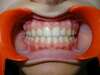

Intrabuccale face - Fin de traitement (16-10-2023) - 63